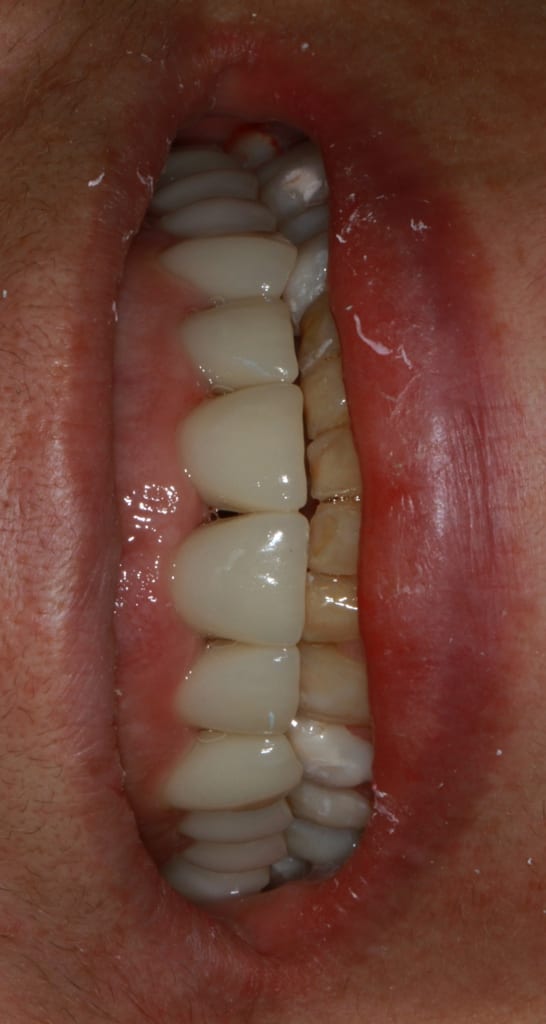

Img 6107 dpg3by - Eugenol

Img 6108 v9ehr3 - Eugenol

Img 6110 b83adw - Eugenol

enlaye

09/02/2018 à 12h32

ayé , je les ai mises .

ah ouiii , mais bouche fermée , ça fait 1 peu cachotteries :-)

j 'ai compris , tu as fais les secteurs post du bas jusqu'aux canines en prov en fonction de ton haut . , et apres tu vas voir ce qui se passe .

bon j'te rassures il ne se passera rien de spécial puisque tes prov de sur-elevation font fonction de gouttierre de relaxation . par contre tes canines vont avoir une forme de talon de santiag .

finalement tu fais par le haut , à la fois l'esthetique et la ( les ) fonction , puis tu adapteras le bas en fonction de la place disponible .